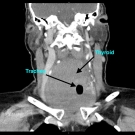

A 61-year-old man was admitted to the inpatient service at a trauma center after having sustained injuries in a motor vehicle accident.

09/09/2019